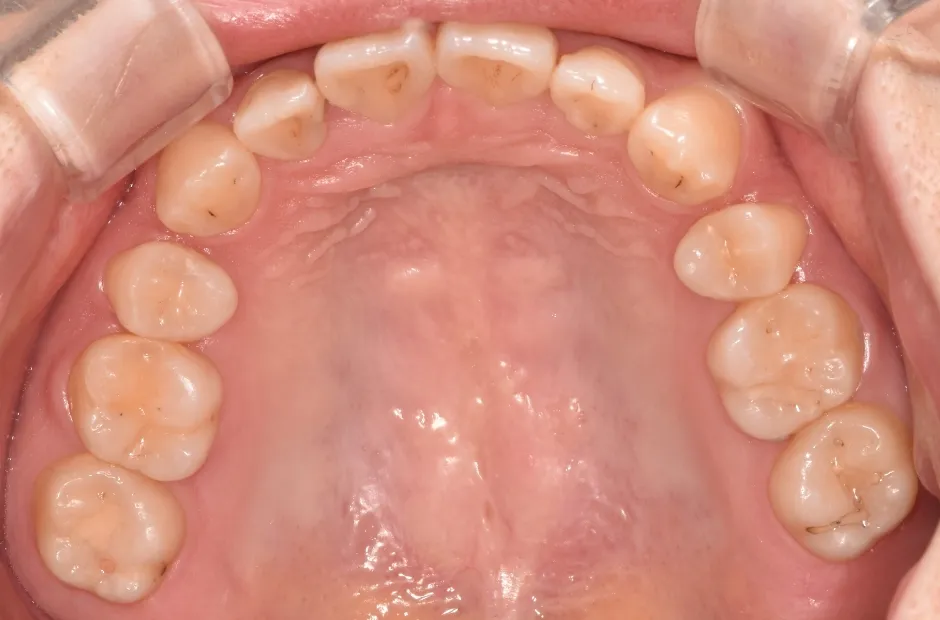

叢生

| 診断名・主訴 | 叢生 |

|---|---|

| 年齢・性別 | 43歳・女性 |

| 治療期間・回数 | 2年7か月 27回 |

| 治療に用いた主な装置 | 舌側矯正 |

| 抜歯部位 | 両顎4,4 |

| 治療費 | 100万円(税抜) |

| リスク・副作用 | 装置による違和感・疼痛・歯肉退縮・歯根吸収・虫歯のリスクなど |

治療前